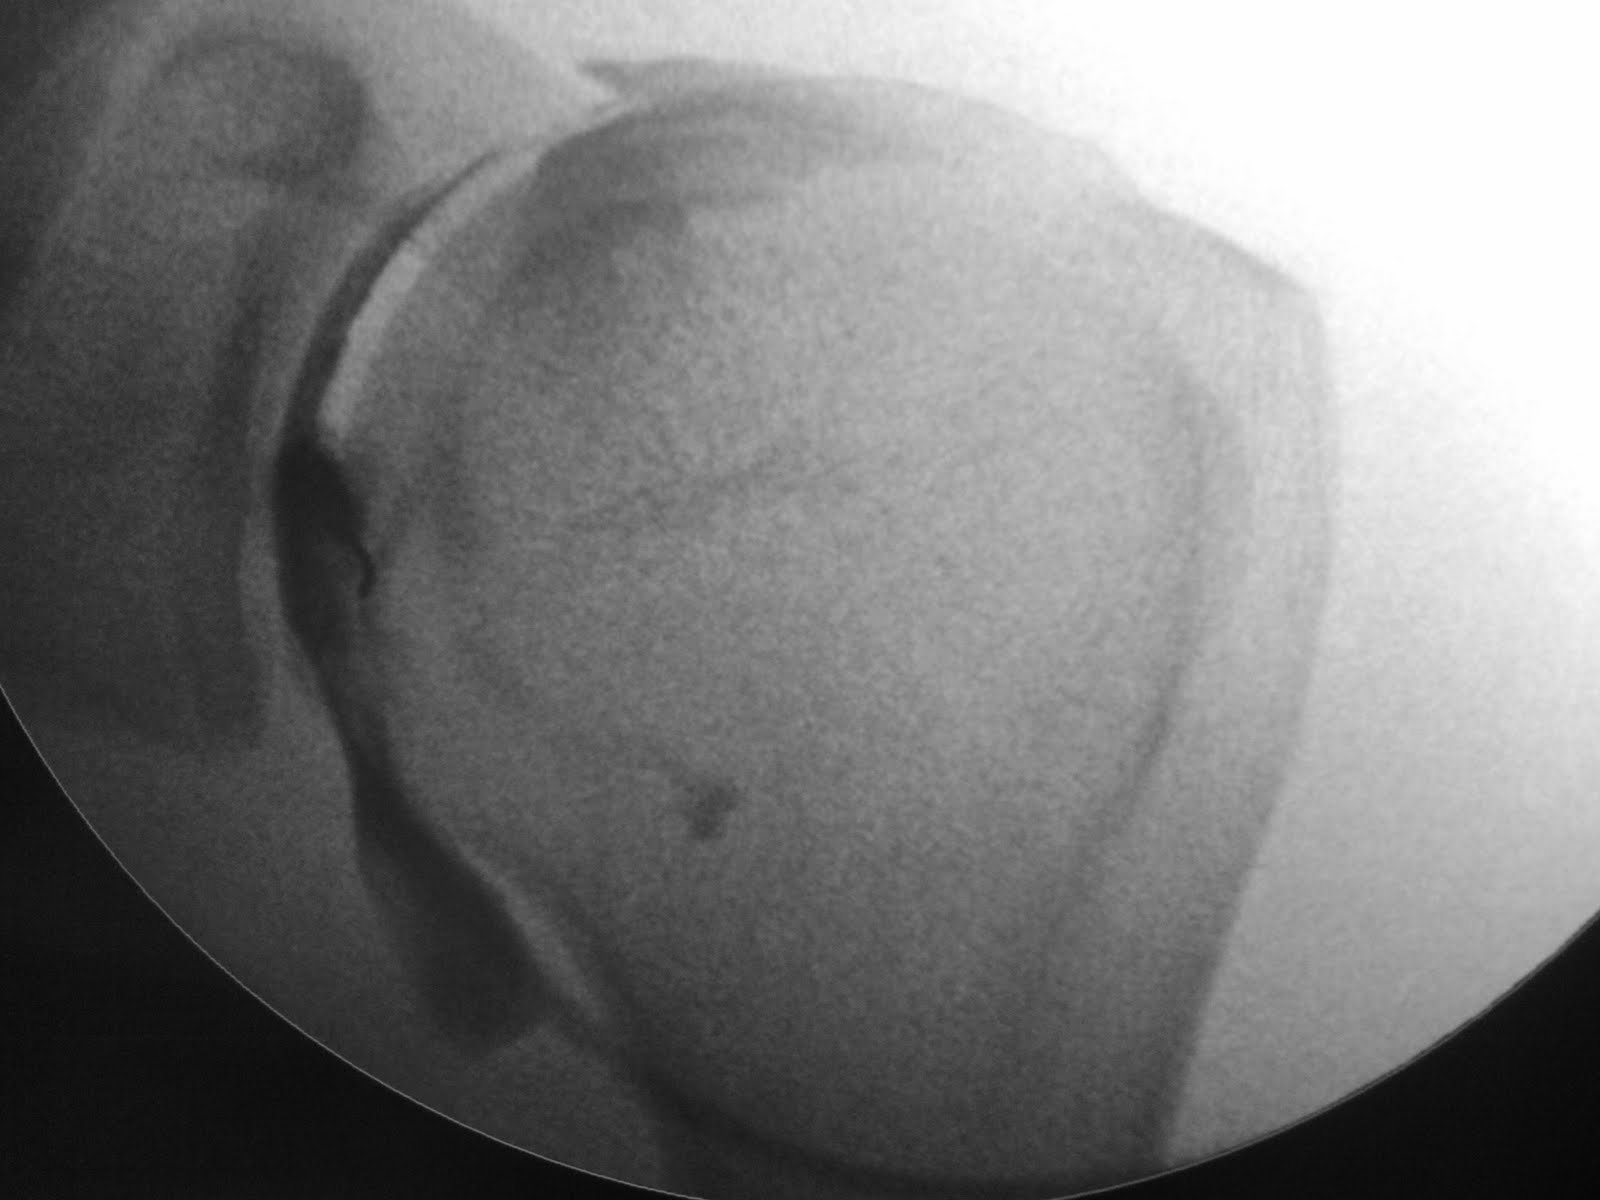

Series of images. First image showing contrast flowing away from the needle into inferior recess. When dilued Gd is injected the iodinated contrast flows into the biceps tendon sheath.